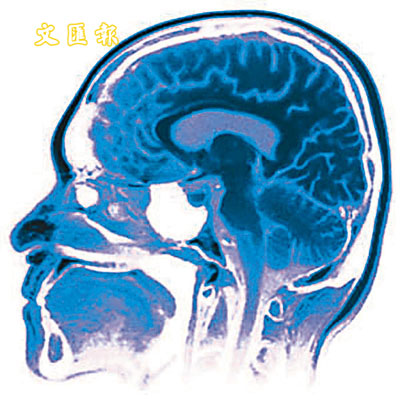

¡@¡½©Ò¿×¡u¦ü´¿¬ÛÃÑ¡v¡A­ì¨Ó¥u¬O¤j¸£¤¤ªº¡u¬üÄR¿ùı¡v¡Cºô¤W¹Ï¤ù

¡@«Ü¦h¤H³£´¿¤£¤î¤@¦¸Ä±±o¦n¹³¤w¨£¹Lªì¬ÛÃѪº­¯¥Í¤H©Î¨ì¹L¤@­Ó·s¦a¤è¡A¤ß²z¾Ç®a§â³oºØ©Ç²§·Pı§Î®e¬°¡u¦ü´¿¬ÛÃÑ¡v¡A¦ý«o¨S¦³¤H¯à°÷¸ÑÄÀ¨ä¤¤²z¥Ñ¡C³Ìªñ¡A¬ü°ê³Â¬Ù²z¤u¾Ç°|¬ã¨s¤p²Õ²×©ó´¦¶}³o¤@¯«¯µ­±¯½¡A«ü¥X¤j¸£ªº¤@­Ó¯S©w°O¾Ð½u¸ô¡A¥i¯à´N¬O²£¥Í³oºØ©_©Ç·Pıªº­ì¦]©Ò¦b¡C

¡@¬ã¨sÅã¥Ü¡A¡u¦ü´¿¬ÛÃÑ¡v¬O¤@ºØ°ò©ó¤j¸£°O¾ÐªºÃþ¦ü¿ùıªº·Pı¡C¨´¤µ¬°¤î¡A¯«¸g¾Ç®a¤w¸g»{ÃѨì¤HÃþªº°O¾Ð¥Ñ³\¦h³¡¤À²Õ¦¨¡A¨ä¤¤¥]¬Aªø´Á©Mµu´Á°O¾Ð¥H¤Î¹ï¨t¦C¨Æ¥óªº°O¾Ð¡A°O¾Ð¬O°ò©ó²{¹êªº¡A¨ä§Î¦¨²o¯A¨ì¤j¸£ªº¤£¦P³¡¦ì¡C

¡@¯«¸g¾Ç®a»{¬°°O¾Ð¨ä¹ê¬O¥Ñ²³¦h¸£²Ó­Mºc¦¨¡A¸£²Ó­M¤§¶¡³q¹L·¥±jªº¤Æ¾Ç¤ÏÀ³¤¬¬ÛÁpô¡A­n·Q³ê¿ô°O¾Ð»Ý­n©w¦ì©M¨ë¿E¬Y²Õ¸£²Ó­M¡C¹ï¤j¸£¨Ó»¡¡A²M·¡°O¾Ð¤§¶¡¦³¬Û¦ü©Ê³o¤@ÂI«Ü­«­n¡FµM¦Ó¡A¯à°÷¤À²M¬Û¦ü¦ý¤£§¹¥þ¬Û¦Pªº°O¾Ð¤]«Ü­«­n¡C

¡@§K¬Ì¿ò¶Ç¾Ç¿Õ¨©º¸¼ú±o¥D§Q®Ú¤t¶i¦h¦~«eµo²{¤F©Ò¿×¡u¼Ò²Õ¤ÀÂ÷¡vªº¬ÛÃö¾÷¨î¡A³o­Ó¾÷¨î¯à°÷Åý¤H³q¹L¬Y­Ó´£¥Ü¦Ó§ä¦^¥þ³¡°O¾Ð¡C¤j¸£¤¤ªº¡u¼Ò²Õ¤ÀÂ÷¡v¦³®É·|¥¢ÆF¡AÅܦ¨·sÅéÅç©M°O¾Ð¦ü¥G§¹¥þ¬Û¦P¡C¥L»¡¡G¡u§Ú­Ì²£¥Í³oºØ©_©Çªº·Pı¡A¥D­n¦]¬°¤j¸£¨â­Ó³¡¤Àµo¥Í¤F½Ä¬ð¡A·s¤j¸£¥Ö¼h§i¶D§A¥H«e±q¥¼¹J¨ì¹L³oºØ±¡§Î¡A¦ý®ü°¨ª¬¬ð°_«o§i¶D§A´¿¸g¹J¹L¡C¡v ¡]³\´Ë¡^